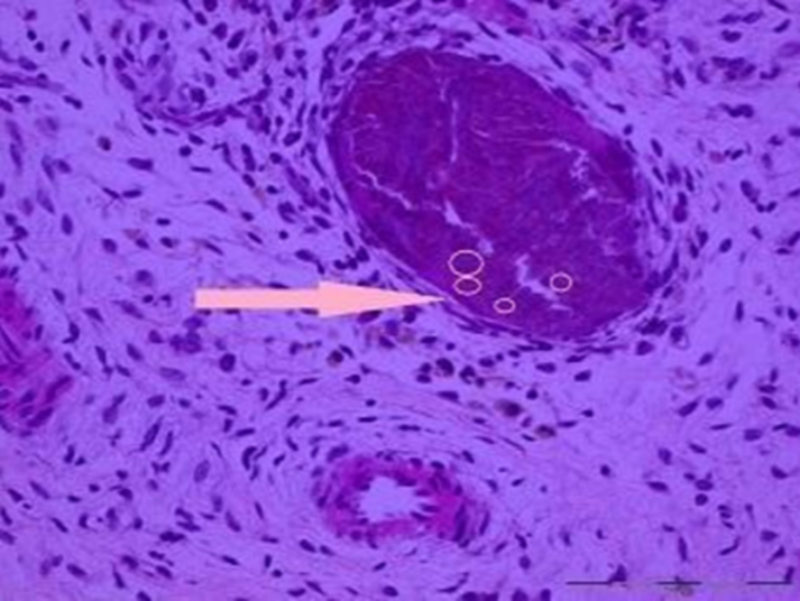

该病诊断的金标准:关节滑液中发现CPPD结晶。

图4.膜组织内见多灶、团块状紫蓝色钙化结晶体沉积